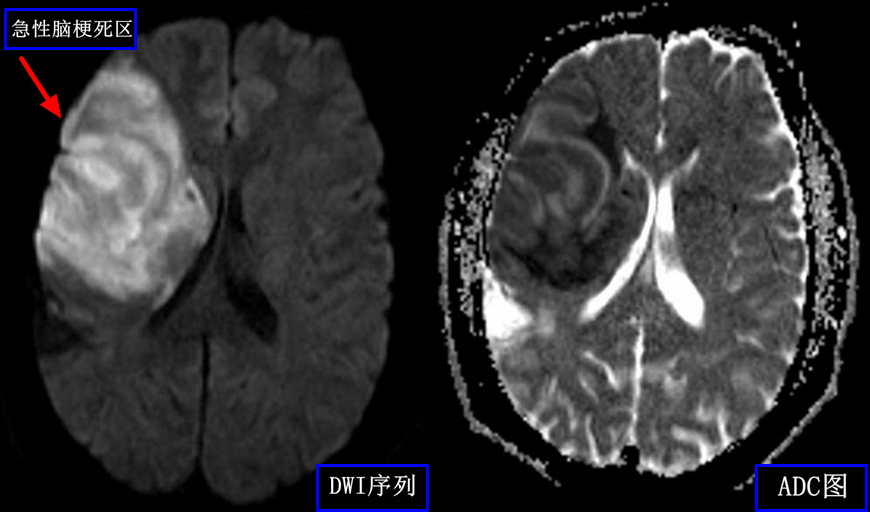

软组织疾病如肌肉选核磁检查。MR与X线的成像原理不同,对软组织的分辨率远高于CT和X线,能用来观察神经、脊髓等椎管内软组织,因此可以用来检测和诊断中枢神经系统疾病、腰椎间盘后突。(如下图为急性脑梗死患者磁共振功能成像DWI,很容易发现梗死病变)

乳腺dr能检查什么【科普】DR、CT、MR?放射科检查项目选哪个好?_https://www.jmylbn.com_新闻资讯_第4张